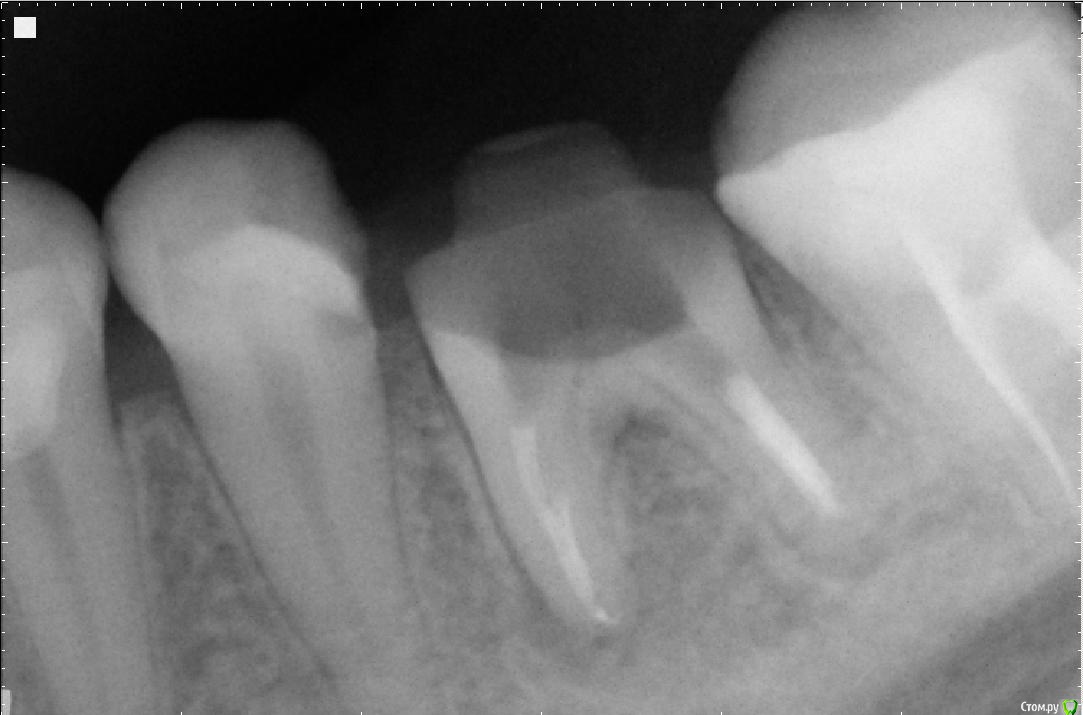

Сашуля Опубликовано 8 декабря, 2016 Поделиться Опубликовано 8 декабря, 2016 (изменено) Здравствуйте уважаемые стоматологи.Очень хочется получить совет.Имею хронический периодонтит. Температура 37,3 постоянно, впрочем, это мне не мешает.Первое фото. Когда обнаружили периодонтит. 2013 год.Второе фото-в процессе лечения.Мне запломбировали каналы, постави вкладку, налили пластиковую временную коронку и отправили в свободное плавание. Зуб никак не беспокоил.Наблюдалась, делала снимки с определённой периодичностью. Зуб не беспокоил.Сейчас настал решающий момент. Последние два снимка были сделаны сегодня. Сторона с проблемным зубом ноет, непонятно, что это болит, толи соседние зубы, толи периодонтит беспокоит. Боль усиливается к вечеру. При надавливании на проблемный зуб острая боль. При внешнем осмотре всё в норме.Вообще грозятся удалять или сделать Гемисекцию. Чего мне ожидать, может быть можно по данным снимкам чтото выяснить.Спасибо. Изменено 8 декабря, 2016 пользователем Сашуля Ссылка на комментарий

Сашуля Опубликовано 9 декабря, 2016 Автор Поделиться Опубликовано 9 декабря, 2016 (изменено) Можно убрать проблемную половину зуба, но со второй половиной ничего толкового не сделать потом. тупиковый путь. У вас 2 варианта.извлечение вкладки и перелечивание зуба либо удаление и имплантация. +1 +Всем спасибо за ответ.Сделали мне снимок и обнаружилась киста. В клинике хирургов не оказалось, один в отпуске второй в Америке. Сказали либо удалять кисту и попробовать оставить зуб либо удалять зуб.Сейчас попробую извлечь снимки. Или если болит с кистой, то только удалять? Изменено 9 декабря, 2016 пользователем Сашуля Ссылка на комментарий

Сашуля Опубликовано 12 декабря, 2016 Автор Поделиться Опубликовано 12 декабря, 2016 (изменено) Увы, киста была слишком большого размера, 7 - 8 мм, не подлежащая лечению. Всё, сильно воспалённое, удалили.Но, у всех специалистов разное мнение.... Будет имплант. Изменено 12 декабря, 2016 пользователем Сашуля Ссылка на комментарий